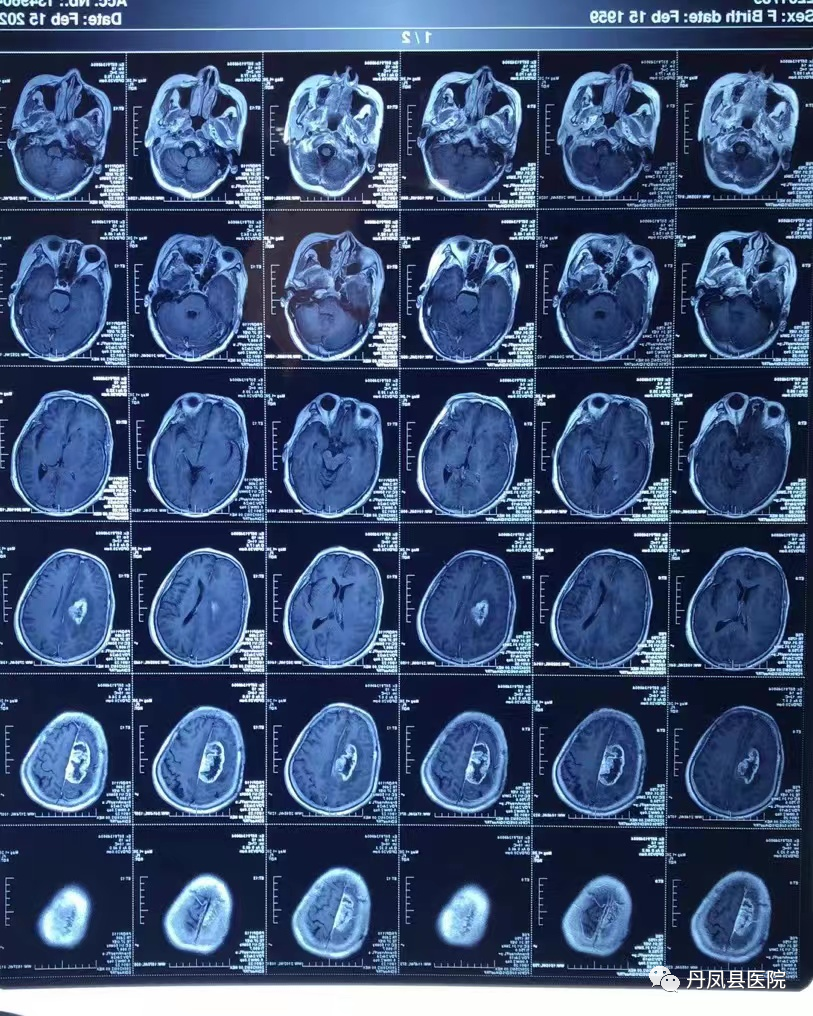

2月22日,63岁的患者黄某,因“左侧肢体活动不灵伴言语不清3月”之主诉来我院外二科就诊。入院后行颅脑CT平扫提示“颅脑占位性病变”,进一步行MRI平扫、增强及MRS成像,考虑“颅内胶质瘤”。因病情危重,急需行大脑镰旁深部肿瘤切除术以降低颅内压,进一步明确诊断。

图为术前CT显示:肿瘤位于大脑镰旁深部外二科王龙珍主任医师、刘建锋主治医师将患者的病情向其家属做了详细的解释,就手术难度及风险、手术团队技术水平及优势、手术紧急并发症应急预案等情况一一向家属说明。细致的沟通获得了家属的赞许和信任,在征得家属同意后,决定为患者实施“幕上开颅:大脑镰旁深部肿瘤切除术”。